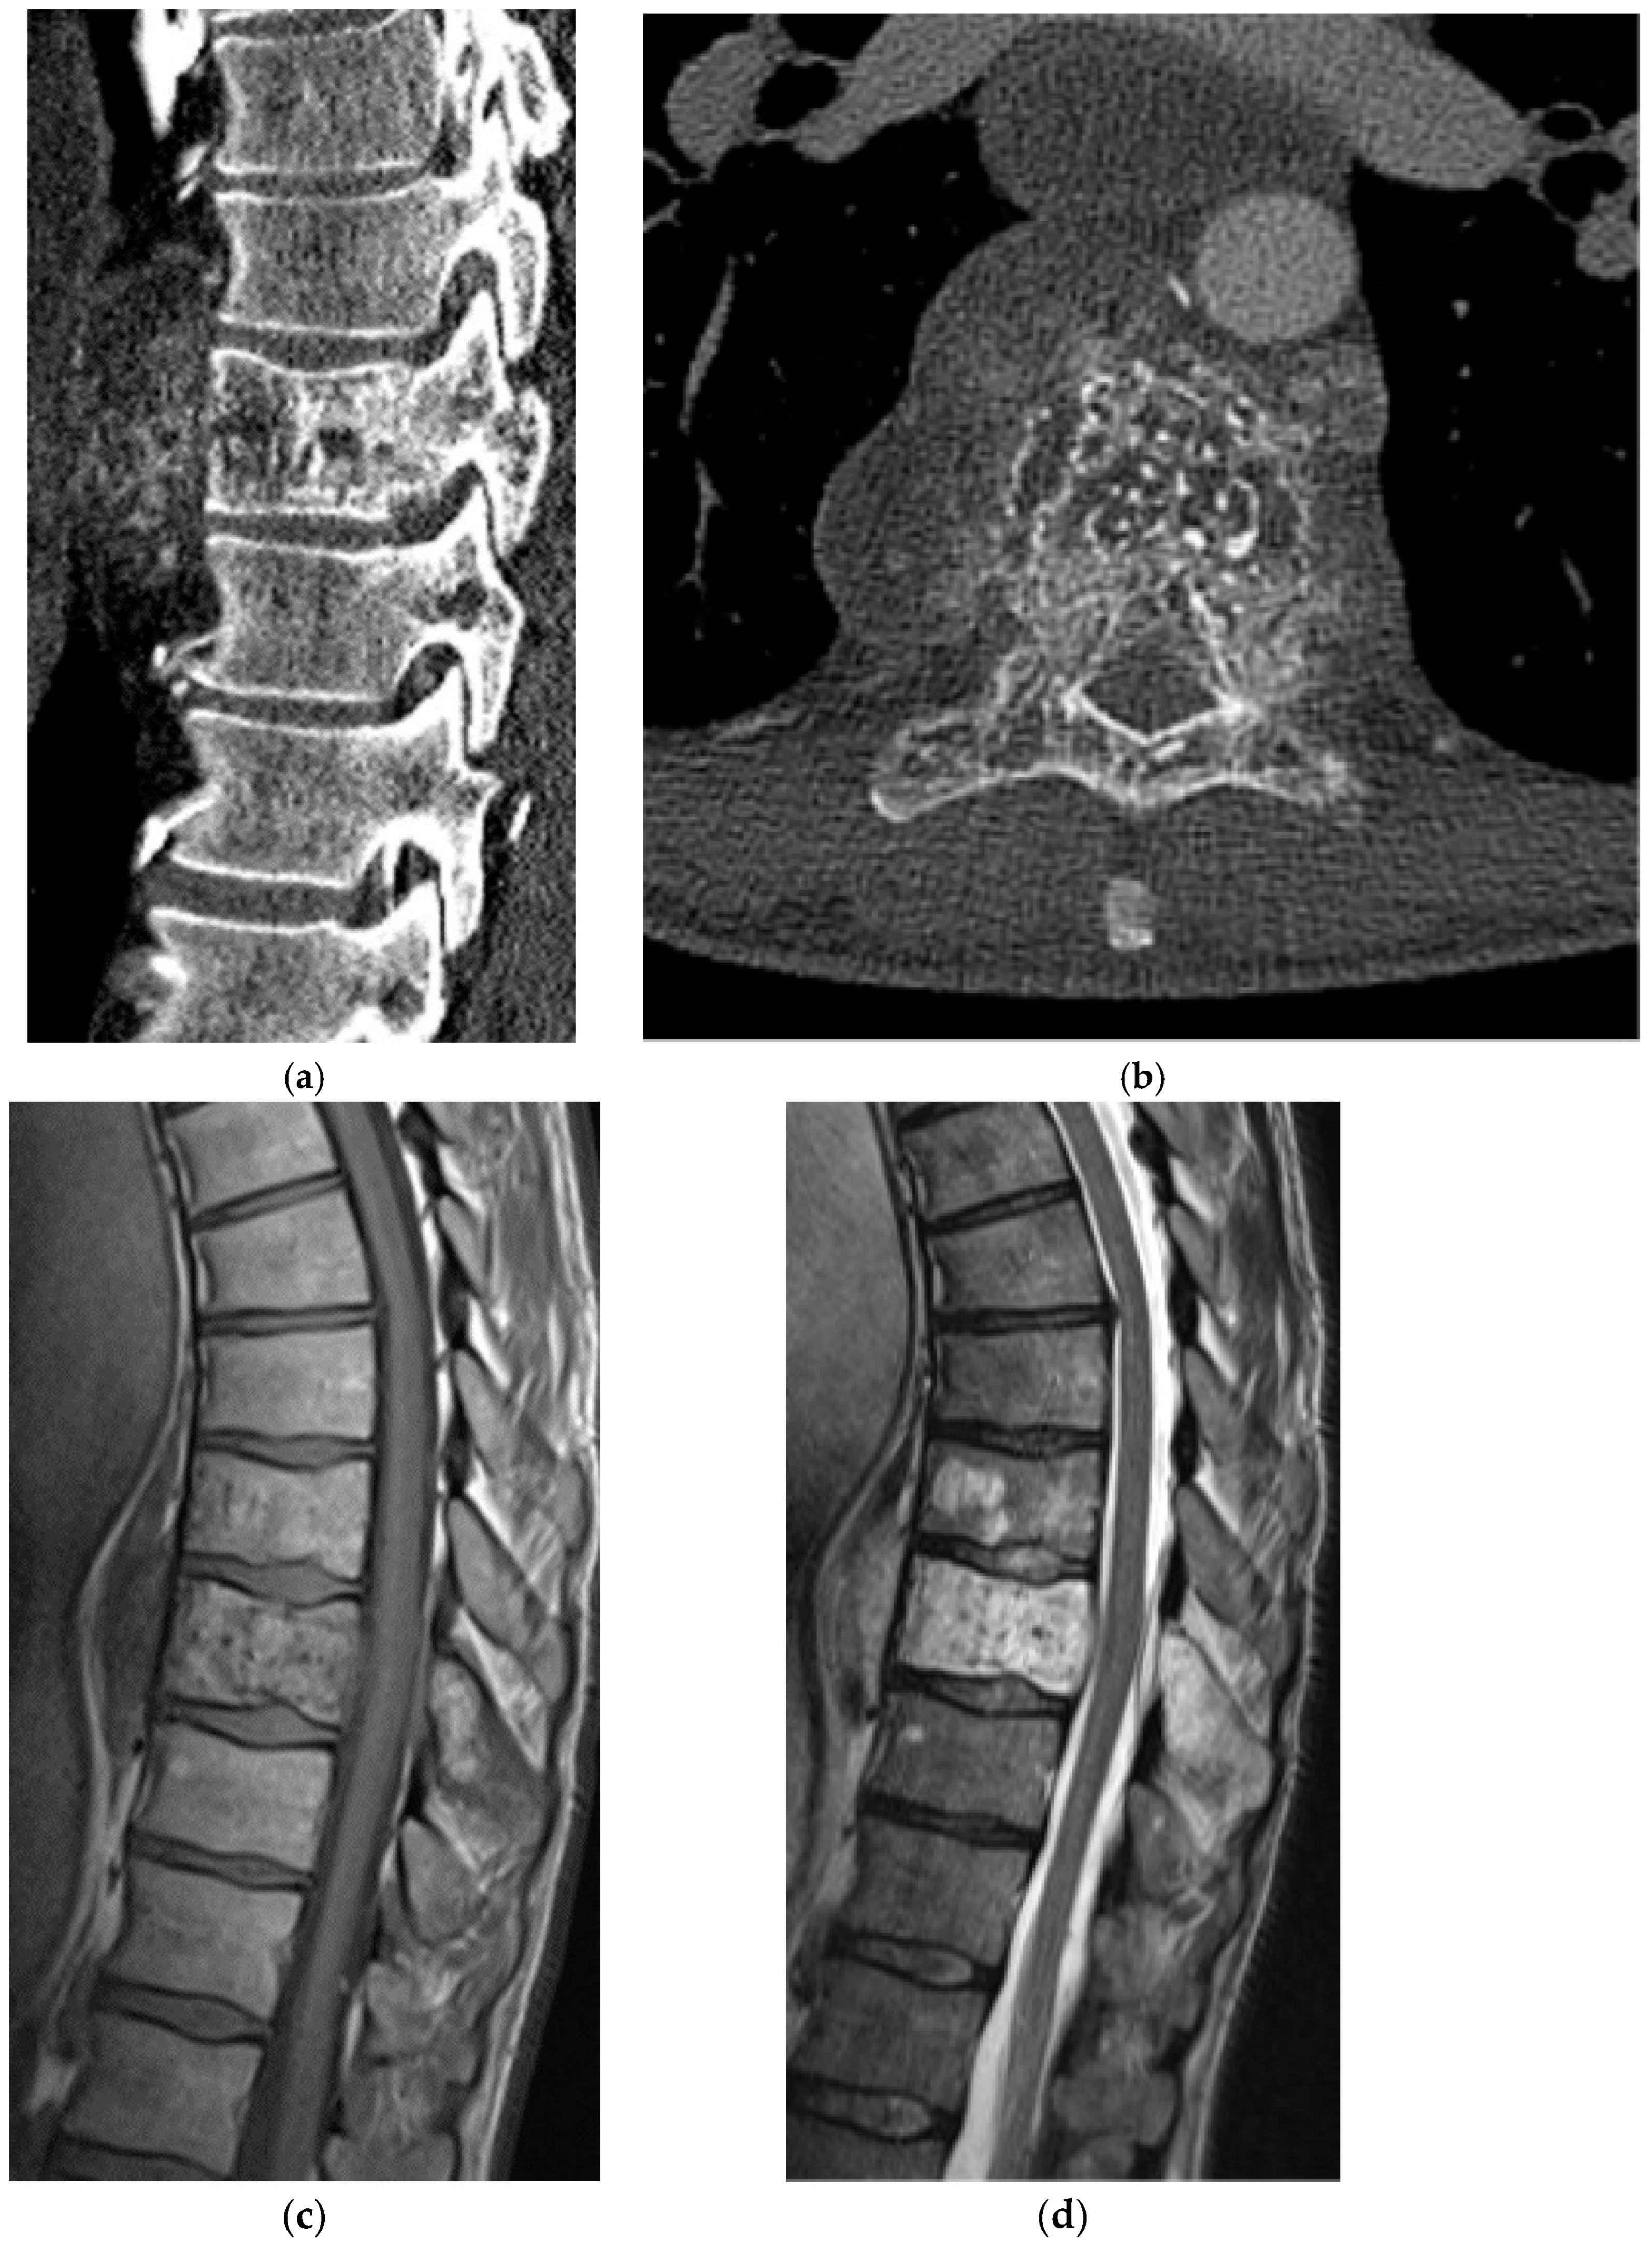

2.2.3. Chondrosarcoma